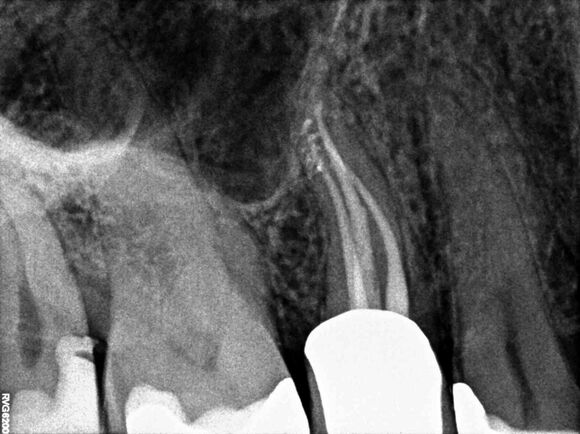

Beispiel 8: Vorher

Schwierige Situation nach einen Unfall bei einem Kind - Wurzelwachstum noch nicht abgeschlossen - Füllung mit MTA - ausgedehnte Entzündung und Beschwerden.

Beispiel 8: Nachher

6 Monate später - Entzündung komplett weg und Beschwerdefreiheit.